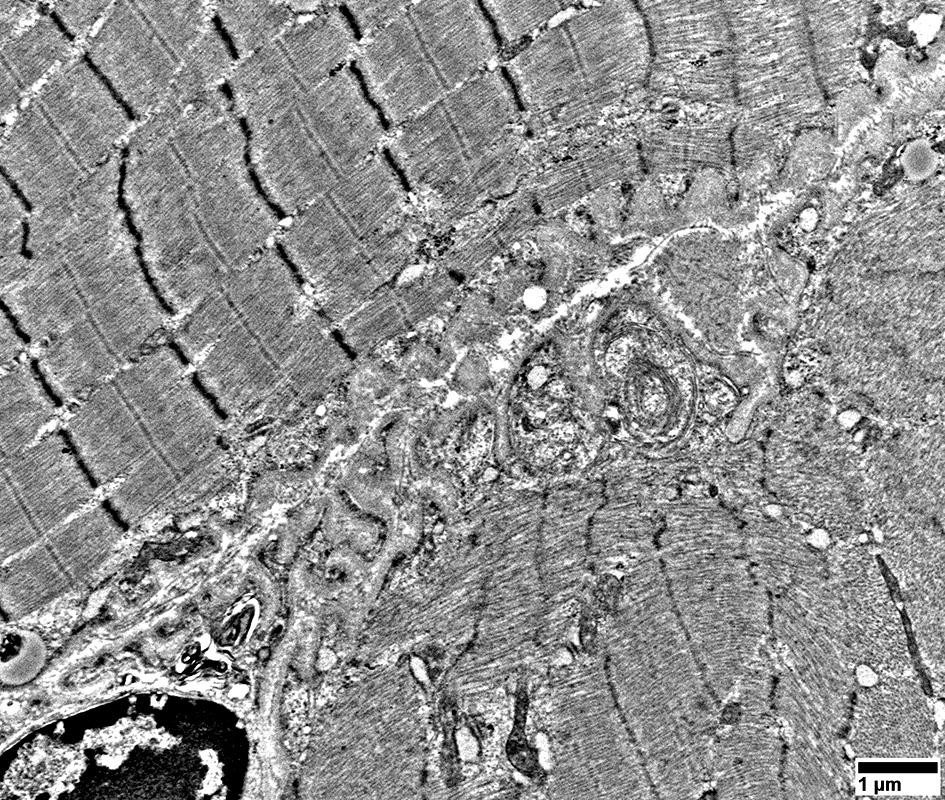

Mitochondrial proliferation between sarcomeres

From: R Schmidt

Muscle fiber basement membrane

Thick

Undulating

Mitochondrial proliferation & enlargement: Beneath muscle fiber surface